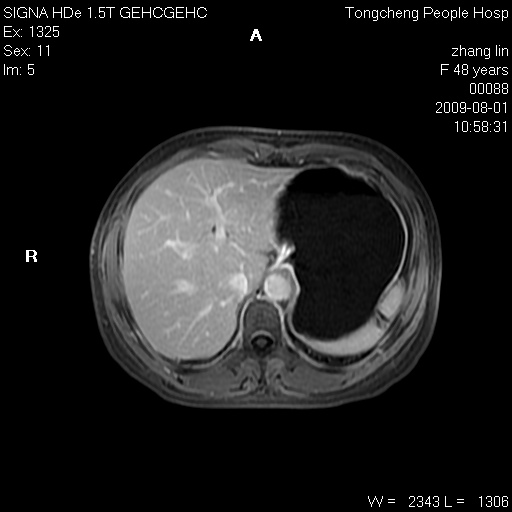

女,48岁。健康体检,彩超发现右肾占位性病变。平素健康。

临床诊断:右肾占位性病变,性质待定(囊肿?肿瘤?)。

上中腹部mr平扫+增强扫描,图像如下:

右肾上极见一类圆形病灶,t1wi呈等信号t2wi呈等高混杂信号,三期增强无强化,边界清---考虑囊肿出血。

同反相位均表现为等信号,病变无强化,考虑含蛋白的囊肿可能,弥散加权相或许有些帮助,